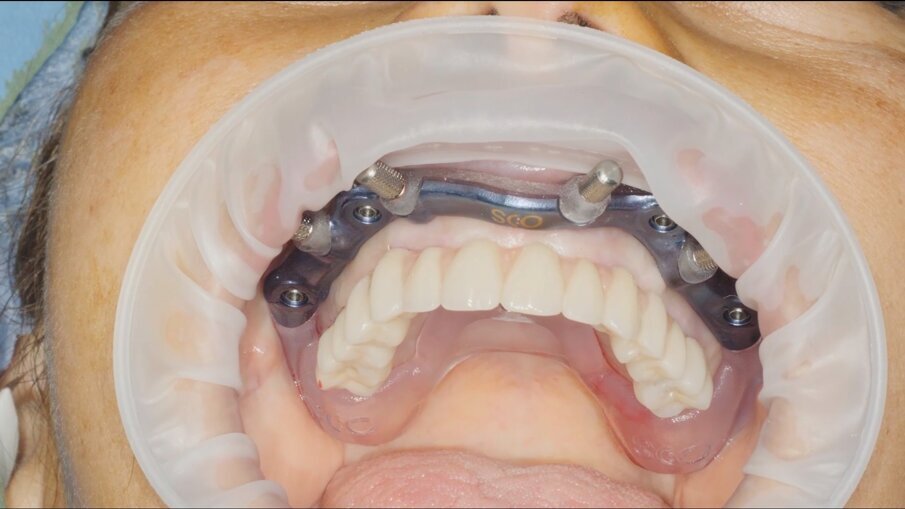

Veniamo quindi al posizionamento della protesi mediante carrier, a sua volta ancorato agli stessi punti di fissaggio della dima base. È significativo osservare come la stabilizzazione della sola vite palatale consenta l’allineamento perfetto tra i sistemi di fissaggio (Fig. 22), mentre il dettaglio mostrato in Fig. 24 illustra efficacemente come prima della cementazione della protesi l’accoppiamento e la centratura del foro protesico appaiano perfetti, confermando quindi come l’obiettivo di alloggiamento della protesi nella sede prestabilita sia stato colto. Per la fase di cementazione con cemento duale si è prestata attenzione alla realizzazione di un foro aggiuntivo per permettere al materiale di raggiungere gli abutment. I fori di accesso alle viti vengono tappati con filo di teflon (Figg. 25, 26) ed è a questo punto possibile andare a fissare la protesi e rimuovere il sistema carrier (Fig. 27). Lasciamo la dima in posizione, così che nell’eventualità in cui un abutment non dovesse essere stato cementato correttamente, ci riserviamo la possibilità di riprendere il posizionamento strategico dell’intero sistema Pcube, intercettando possibili impedimenti alle manovre di finalizzazione del caso.

Fig. 22

Fig. 23

Fig. 24